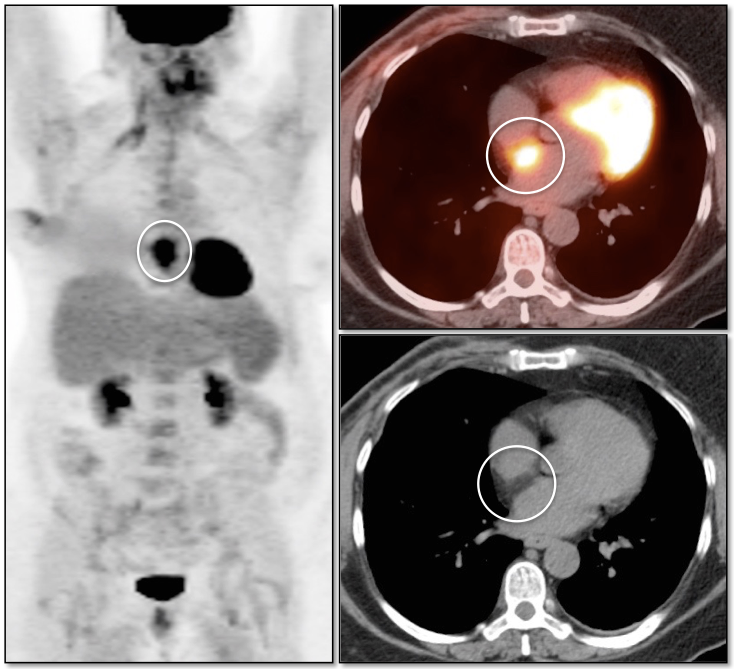

Lipomatous Hypertrophy of the Inter-Atrial Septum

LHIAS is focal fatty infiltration of the inter-atrial septum of the heart. It behaves as hypermetabolic brown fat, and is often intensely FDG-avid, appearing mass-like on the PET images.

Although a non-malignant finding, there are reports of a rare association with arrhythmias.

Diagnosis of this hypermetabolic PET finding is confirmed by the presence of only fat on the co-registered CT images.

Misdiagnosis of this “Aunt Minnie” is unacceptable (as in the terrified patient referred to us from Europe, who flew in with his images to further evaluate his “heart cancer”).

Although benign, we recommend mentioning this finding in the body of the report, as it often looks impressive on the PET images and can prompt a call from a clinician concerned that you “missed” a mass.

We generally report:

“Incidentally noted is lipomatous hypertrophy of the inter-atrial septum, typically of no clinical significance.”